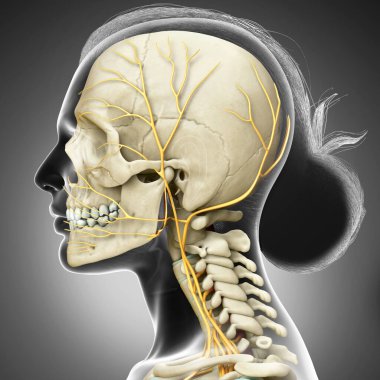

iskelet adam yan görünüm baş ve sinir sistemi

resimlemeİnsanSağlıksağlıklıYaşamkanSağlık hizmetleriTıbbiboğazıçizgi filmsemboldişlerKardiyolojikalpnabızgövdeÇizimbiyolojiBilimbölümgemigerçekçiGöğüsorgBilimselanatomidiyagramPompaGergintedavülarterAtriumApexanatomikSinirlerdolaşımaortkoronerventrikülİnsan Vücududamar sistemiPulmoner fizyolojisiFiziksel bölümdolaşımı kanAnatomi gözlerBenzer İçerikler